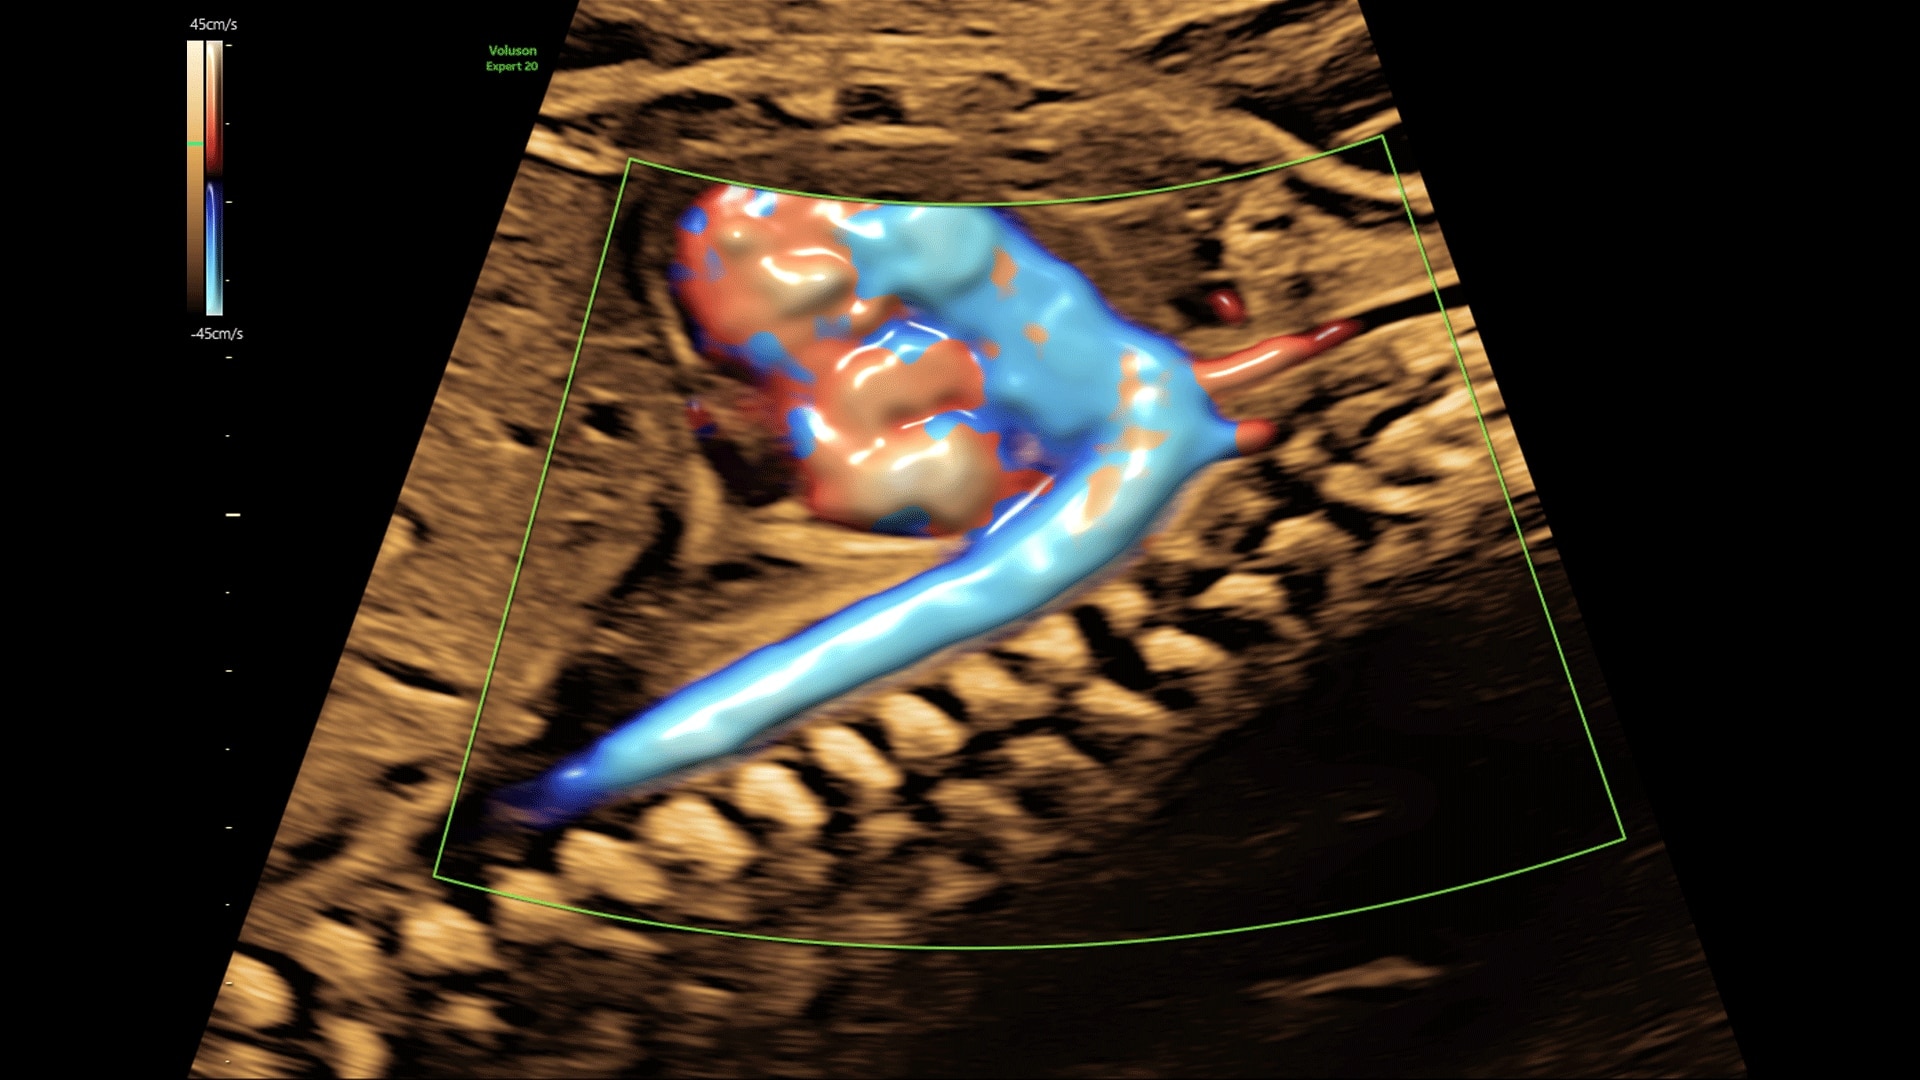

Generate spectacular 2D/3D and color Doppler images with increased penetration and stunning clarity, to help visualize critical details needed for diagnostic assurance. The Lyric Architecture unlocks new imaging and processing power to expand your imaging capabilities for years to come